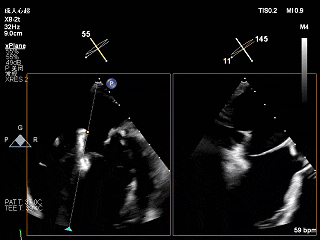

夹子关小进入左心室

瓣下打开夹子确认轴向

倒置夹子,拉回左房,加“-”号调整“hug”,后修正轴向

第二次去到瓣下

夹子下到心室捕捞瓣叶

Gripper down抓捕瓣叶

重新打开夹子,调整位置

第二次捕捞瓣叶

夹子关小后3D观察组织桥